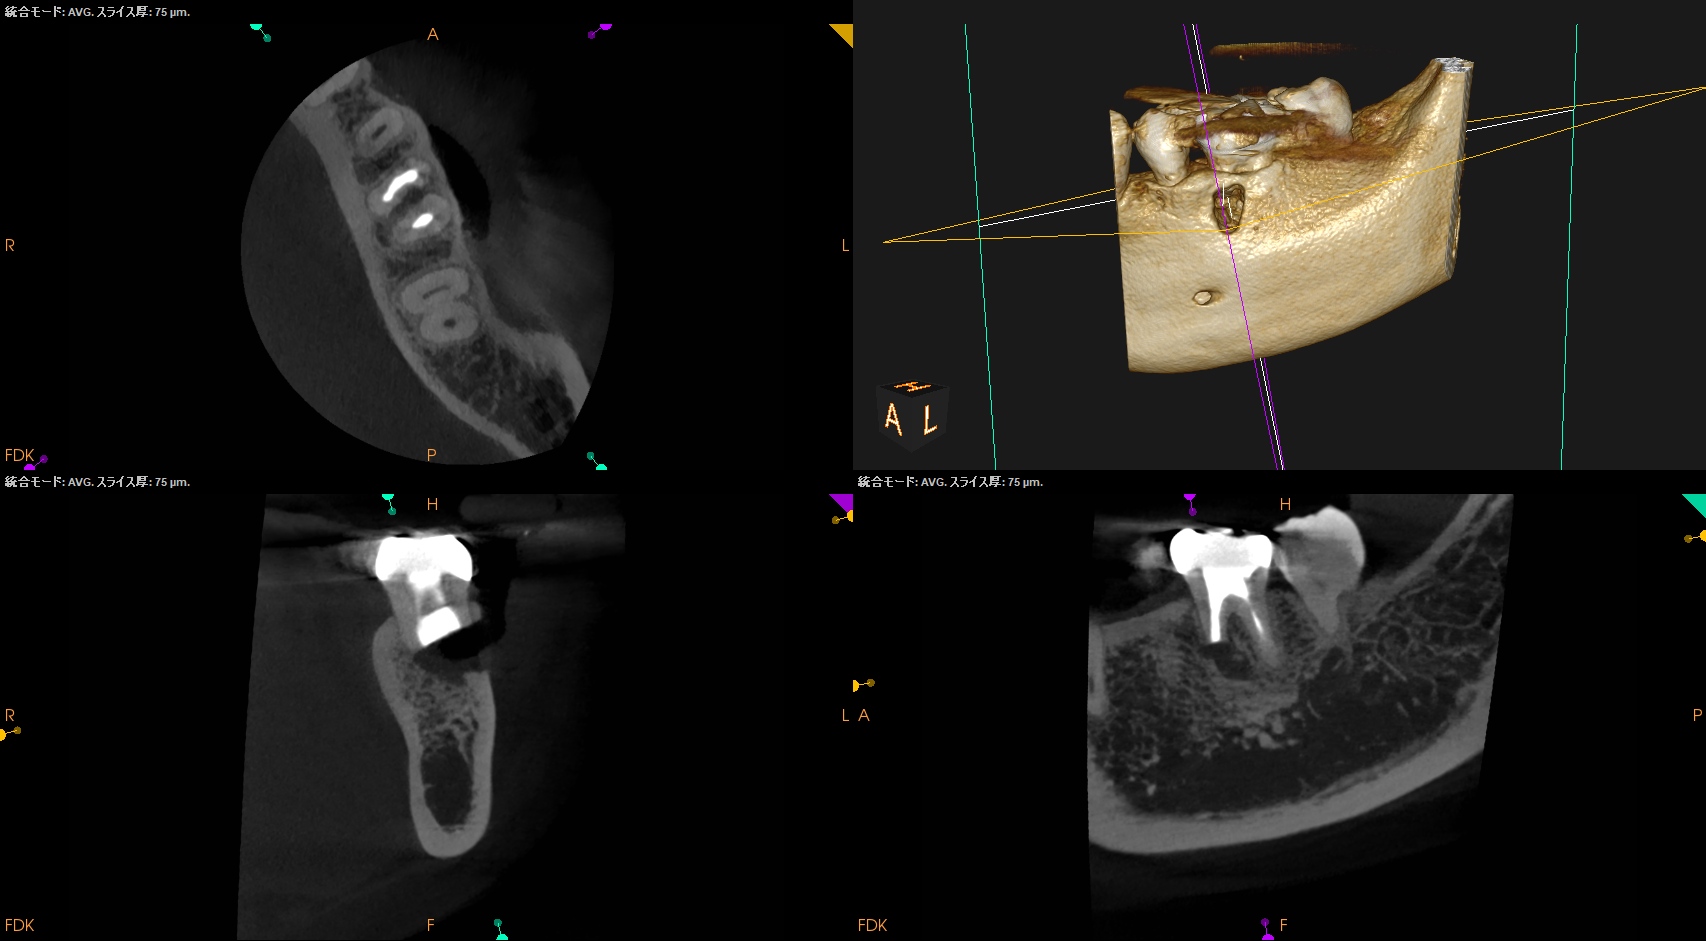

#19 M Apicoectomy(2025.1.9)

当該部位をOsteotomyした。歯槽骨は2mm削合する必要がある。

Apexを3mm削除し取り除いた。

逆根管形成はMB-MLを往復しなければならないが、

間がかなり離れているので逆根管形成には時間がかかる。

逆根管充填するが、その際はペントロンジャパンのエンドセム MTA クイックペースト Rで逆根管充填することにした。

術後にPA, CBCTを撮影した。

問題はないだろう。